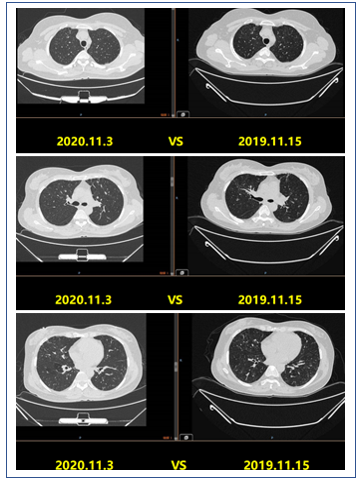

患者转归

图17 2019年3月11日患者胸部CT